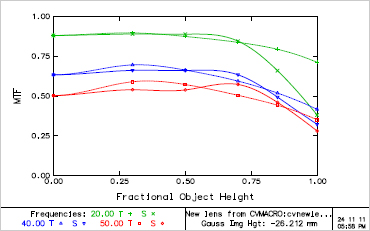

- MTF(Field)